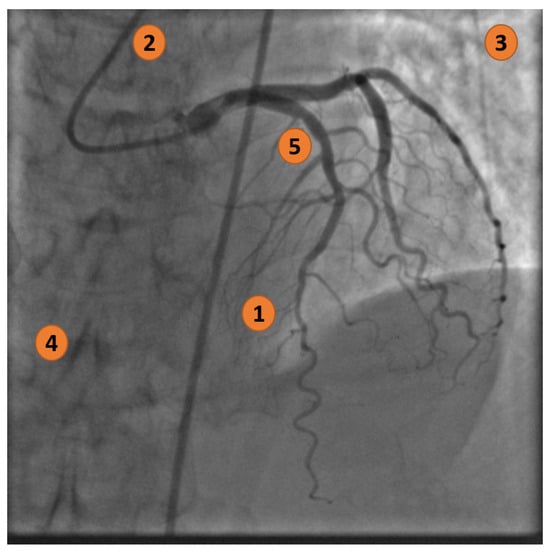

Figure 2 highlights five main visual complications when examining an XCA image (from the ICA dataset).

Figure 2. X-ray coronary artery with the following characteristics: (1) Zones with a low signal-to-noise ratio; (2) Interfering background structures (catheter); (3) Non-uniform illumination; (4) Artifacts and noise; and (5) Vessel junctions and bifurcations.